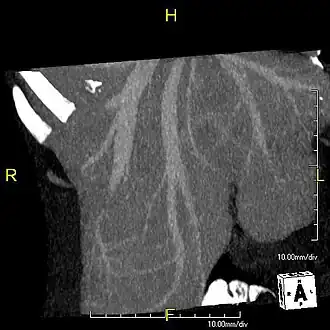

-

Axial CT image showing anomalous hepatic veins coursing on the liver's subcapsular anterior surface[74] -

Maximum intensity projection (MIP) CT image as viewed anteriorly showing the anomalous hepatic veins coursing on the anterior surface of the liver -

Lateral MIP view in the same patient as previous image -